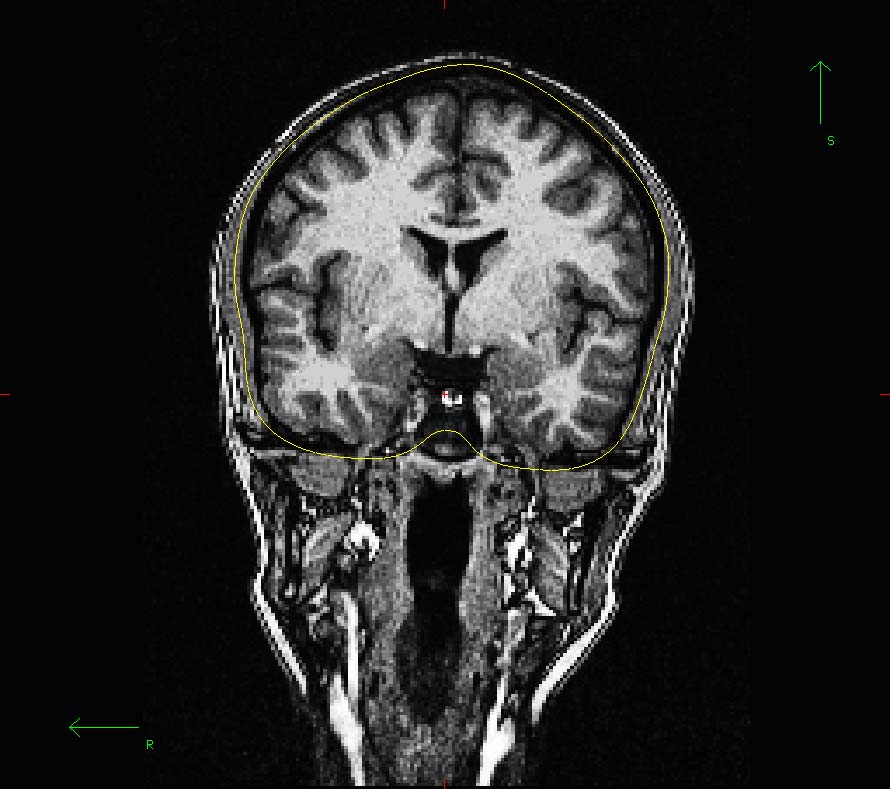

Innerskull in tkmedit

I could load in only the sub10_inner_skull_surface file (output of mne_watershed_bem) in tkmedit overlayed on the T1.mgz.